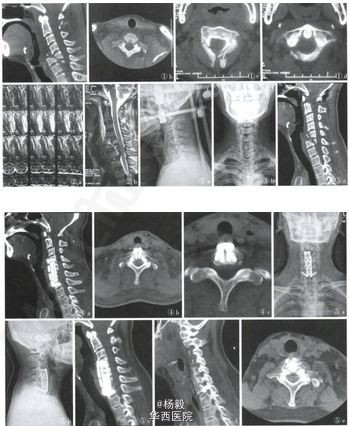

前路反向椎弓根螺钉复位固定下颈椎多节段骨折脱位合并椎弓根骨折

男性患者,49岁,因“车祸致头部流血伴头痛、胸闷2h余”急诊来我院就诊。伤后曾短暂昏迷数分钟,醒后不能回忆受伤时情况,并感头痛、恶心,无呕吐、伴颈部疼痛、双上肢麻木、大小便未解。入院查体:神志清,额头有一长约15cm的皮肤挫裂伤口,顶部见2处长约5cm、6cm的不规则伤口,左踝部有一不规则伤口,长约3cm,有活动性出血。颈部有压痛,心脏体检未见明显异常,左肺可闻及湿性罗音。 腹部体检无明显异常。四肢无畸形,双上肢感觉减退,左上肢肌力Ⅱ级,右上肢手指伸屈肌力为Ⅳ级,屈伸肘肌力正常,病理反射未引出。入院X线片示C5-6椎体骨折脱位;CT示右侧额、顶、颞部头皮血肿;左肺创伤性湿肺,颅内及腹部未见明显异常,C1后弓、C2椎板、棘突骨折,C5-7椎体骨折伴脱位,C6、7双侧椎弓根骨折(图1)。入院后立即行伤口清创缝合止血,抗休克、颈托制动等救治,待病情稳定后,2周后行MRI检查示C5-7椎体骨折伴脱位,C6、C7双侧椎弓根骨折,C6-7水平继发性椎管狭窄,C7至T1椎间盘损伤。 来源:中华创伤骨科杂志2014年第16卷第9期